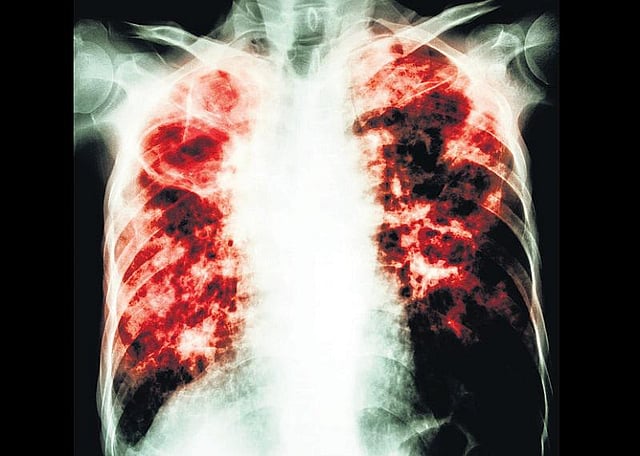

யாருக்கு வரும் உருக்குலைக்கும் நோய்?- காசநோய் விழிப்புணர்வு

டி.பி. எனப்படும் காசநோய்தான். மிகச் சுலபமாகப் பரவும் ஆபத்து கொண்ட இந்த நோய், பாதிக்கப்பட்டவர்களை உருக்குலைத்துவிடக்கூடியது.

பொதுவாக ஒருவருக்குக் காசநோய் இருக்கிறதா என்பதை எப்படி அறிவது? தொடர்ந்து இருமல், சளியுடன் ரத்தம் வருவது, காய்ச்சல், இரவில் குளிர் நடுக்கம், நெஞ்சில் வலி, இரவில் அதிகம் வியர்ப்பது ஆகியவை இந்த நோய்க்கான அறிகுறிகள். இந்த அறிகுறிகள் உள்ளவர்களுக்கு காசநோய் இருக்கிறதா என்பதைச் சளியை எடுத்துப் பரிசோதிப்பதன் மூலம் உறுதிப்படுத்தலாம்.

காசநோயை ஆரம்ப நிலையிலேயே கண்டுபிடிப்பது மிகவும் முக்கியம். அப்படிக் கண்டுபிடித்துவிட்டால் ஆறு மாதங்களில் மருந்து, மாத்திரைகள் சாப்பிட்டு நோயைக் குணப்படுத்திவிடலாம். காசநோயில் மரணம் ஏற்படுத்துவது ‘மல்டி டிரக் ரெசிஸ்டன்ஸ்’ (எம்.டி.ஆர்.-டி.பி.) என்ற நிலையில்தான்.